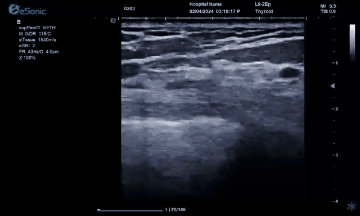

银河官网医疗(ESI)设计的原数精准准台式平台,采用软声束成像系统,采集帧频达到10000Hz/S,每秒处理数据达10亿次,这是超声历史上首次做到准台式机型使用超快速平台。使用此平台,加快了临床图像的帧频采集速度和屏幕显示的刷新速度,获得更加清晰的图像,对女性两腺较细小病灶有较高的细微结构分辨率,有助于增强诊断和治疗决策的信心。

银河官网医疗(ESI)表示,其最新的人工智能功能可以帮助到医疗机构的工作效率,功能包括,实时、动态、快速自动识别病灶,良恶性病灶概率预测,甲状腺结节和乳腺的二维灰阶动态自动实时检测需求,提供多个结节动态检测轮廓框。实时获取多幅具备临床特征(大小、属性等)的结节切面,同时提供当前切面所示结节的结节大小、属性特征、TI-RADS 分级。

对于甲状腺结节相关的自动检测功能,甲状腺结节病灶检出率≥95%,良恶性分类灵敏度≥90%、良恶性分类特异度≥85%。